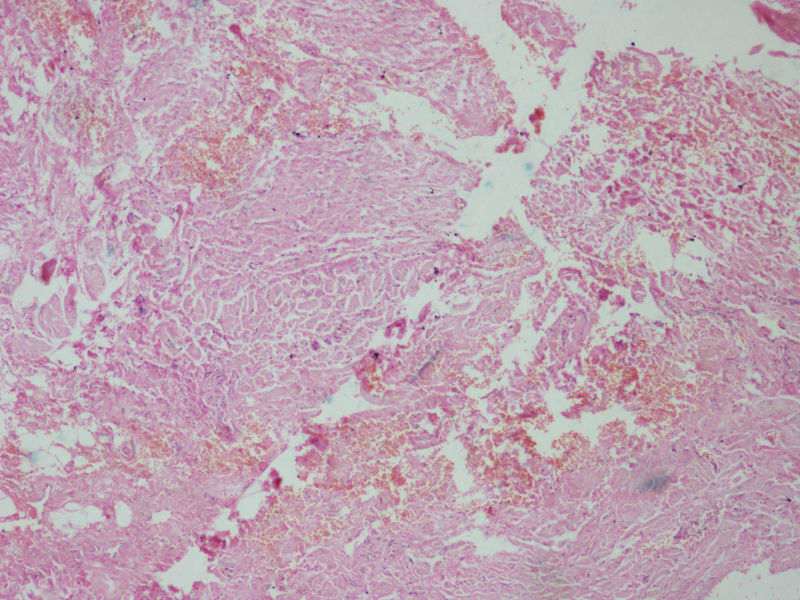

女17岁发现右大腿腘窝处一包块,渐进性增大4年,

• 右大腿包块图2

图2

像血管瘤

肿物多大,有手术史吗?片子染得不太好,图三像异物。

据说肿物很大,但是送来只有黄豆大小,可能是只取了肿物周边的吧